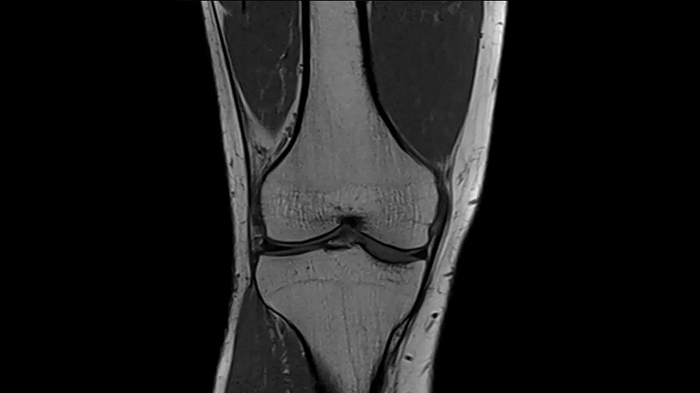

Knee

PD TSE Fat Sat with Deep Resolve and Simultaneous Multi-Slice

For clear imaging of the knee, outstanding fat suppression and performance are possible. Integrating the influence of Deep Resolve with the established Simultaneous Multi-Slice technique.

SMS 2 | Deep Resolve Gain & Sharp

0.4 x 0.4 x 3.0 mm2

TA 2:56 minutes

MAC-ID: 7aaaa0198.

MAC-ID: 7aaaa0198. Image Credit: Siemens Healthineers